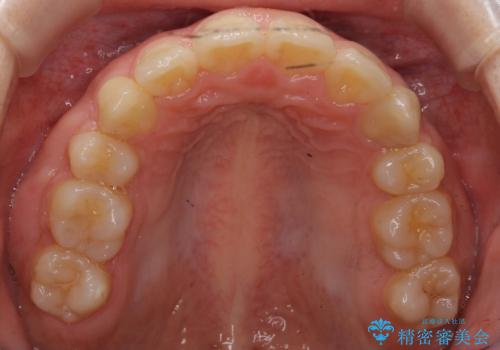

- 矯正装置

- 審美装置

上下左右の小臼歯を抜歯しています。